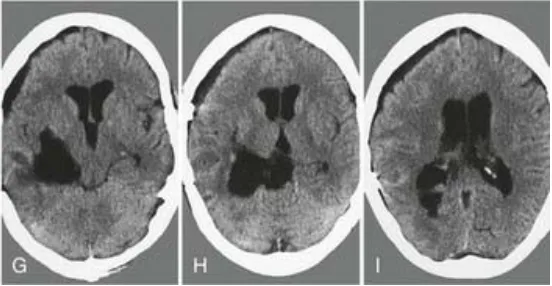

G-I:术后CT证实肿瘤已全切。